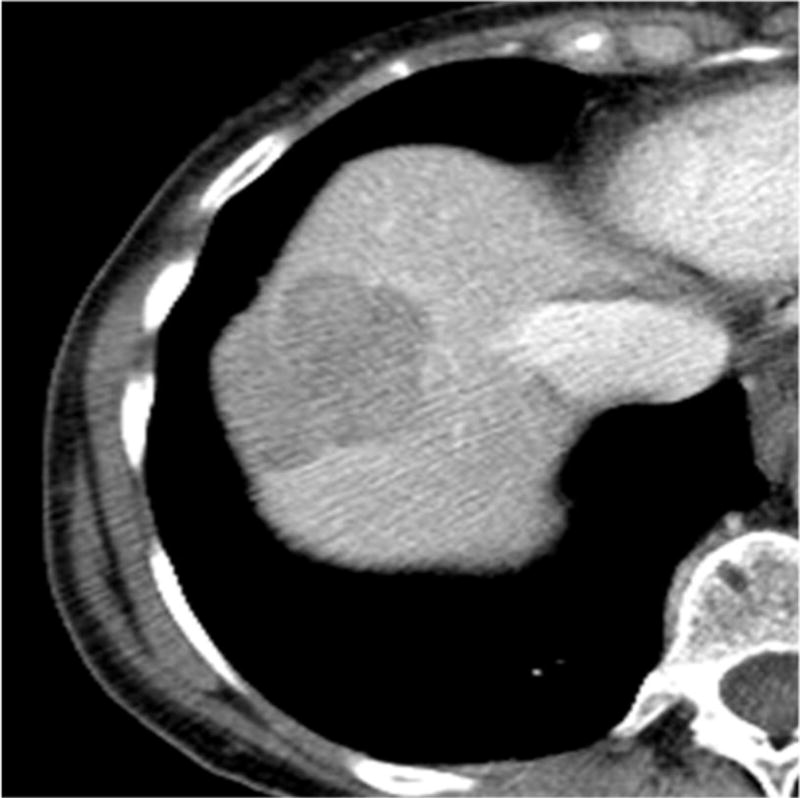

Figure 2.

Images of GIST metastatic to the liver in a 76-year-old man. (a) Axial contrast-enhanced CT scan shows a liver metastasis with maximum diameter of 3.9 cm in the anterior segment of the liver. (b) 3 month after HAE, tumor size decreased and be replaced to non-enhancing area.